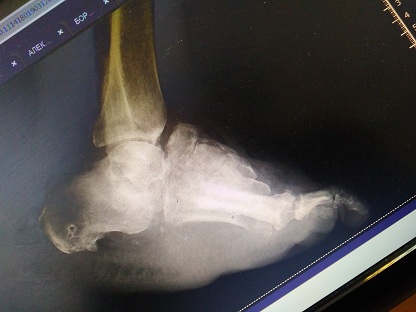

Диабетическая нейроостеоартропатия (ДНОАП) - одно из самых тяжелых осложнений сахарного диабета, требующее сотрудничества ряда специалистов, в том числе травматологов-ортопедов. Однако отсутствует единый подход в выборе тактики ортопедического лечения данной группы пациентов. С 2015 по 2018 гг. включительно наблюдались 35 пациентов с ДНОАП, которые получали консервативное или оперативное ортопедическое лечение. 11 пациентов получали консервативное ортопедическое лечение, хирургическое лечение получили 24 пациента. Всего выполнено 26 оперативных вмешательств. Выполнялось два типа хирургических вмешательств: 1) резекция выступающего фрагмента той или иной кости предплюсны - 12 операций; 2) реконструктивная операция, направленная на коррекцию грубой деформации среднего и/или заднего отдела стопы, - 14 операций. Наряду с общеклиническим обследованием всем пациентам проводились ортопедическое обследование, определение степени нарушения кровоснабжения. Дифференцированный подход к выбору метода ортопедического лечения представленной группы пациентов позволил восстановить опороспособность конечности, обеспечить стабильность в голеностопном суставе и суставах среднего отдела стопы, создать условия для заживления и предотвращения рецидива язвы. Полученный опыт позволил предложить показания для того или иного метода ортопедического лечения деформаций стоп при ДНОАП в зависимости от стадии патологического процесса, его локализации, степени выраженности деформации и клинического течения данной патологии.